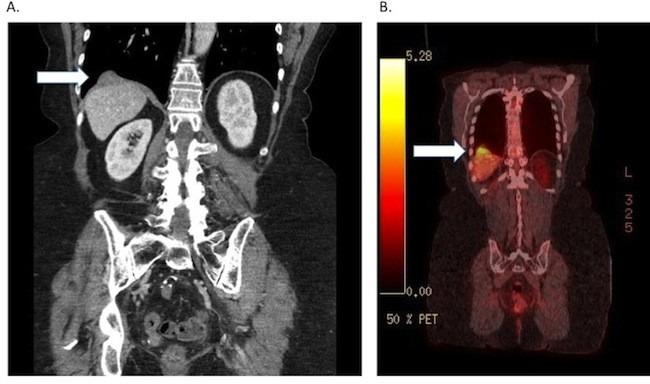

We report a case of optimal quinary debulking for recurrent papillary serous carcinoma of the ovary involving the liver parenchyma through the full thickness of the diaphragm into the lung parenchyma. Multiple debulking procedures for ovarian cancer are controversial, especially when there is extensive upper abdominal or thoracic disease. Selection criteria for such extensive surgery include: good functional status, long disease-free interval, and absence of other systemic disease. Our patient tolerated her procedure well without evidence of residual disease over 6 months postoperatively.

我们报告了一例复发性卵巢乳头状浆液性癌的最佳五期减瘤手术病例,该肿瘤累及肝实质,穿过膈肌全层侵入肺实质。卵巢癌的多次减瘤手术存在争议,尤其是当存在广泛的上腹部或胸部疾病时。这种广泛手术的选择标准包括:良好的功能状态、较长的无病间期以及无其他全身性疾病。我们的患者对手术耐受良好,术后6个月无残留疾病迹象。